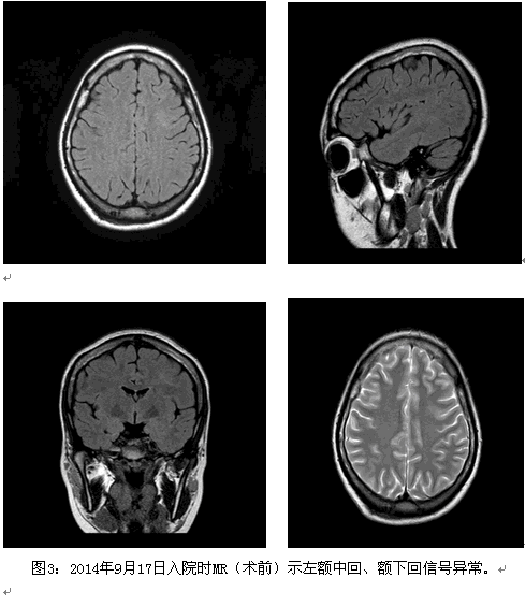

患者考虑为药物难治性癫痫,且曾有发作致脑外伤的事件,纳入术前评估。结合相关检查结果,脑电图报告:异常脑电图III(清醒/睡眠),间歇期:弥漫性,左额-中央著,发作期:临床:右侧偏转。EEG:发作型,左半球。头颅MRI薄层扫描:1.右侧颞叶皮层(含颞极)、邻近右侧额下回多发软化灶并胶质增生、含铁血黄素沉着;右侧额叶眶回局部慢性小出血灶并含铁血黄素沉着可能性大;2.待排左侧额上回与额下回交界处局灶性脑皮质发育不良;3.考虑左侧乳突炎症改变。视野检查无异常。韦氏测试:智商84,言语76,操作96,记忆<51。癫痫定位考虑为额叶外侧面,定侧为左侧,病因考虑皮层发育不良;经全中心讨论后计划一次性切除手术,切除范围,后界:中央前沟后壁,上界:额上沟外侧壁,下界:额下沟外侧壁1cm;前界:额中回后部。予术中唤醒下切除,切除过程中嘱患者讲话并交流,病变质地稍硬,将病变全部切除,约3.5*3.0*3.0cm,术后患者无语言功能障碍,随访近3个月无发作,术后病理回报:局灶性皮层发育不良FCD Ib型。

该患者病变主要位于额中回,为额眼区之一,该患者发作时头眼右侧偏转可能与额眼区的眼球平稳追踪运动相关,而该患者发作时的视觉先兆推测与视觉通路中的某一脑区相关。